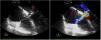

Varón de 82 años, hipertenso y con insuficiencia renal crónica en hemodiálisis, con mala situación basal. Acude por deterioro del estado general de 2 semanas de duración, objetivándose un bloqueo auriculoventricular completo. Ingresa en UCI, estable hemodinámicamente y con oxigenoterapia de bajo flujo. Se realiza ecocardiografía transtorácica, que evidencia una insuficiencia mitral moderada e imagen sugestiva de vegetación en el velo anterior mitral (fig. 1). Hemocultivos positivos para Staphylococcus aureus. La ecocardiografía transesofágica confirma una vegetación de 14×10mm en el velo anterior mitral (A3) y evidencia un pseudoaneurisma (fig. 2,*) en la base del septo interauricular con fistulizaciones múltiples que comunican el tracto de salida del ventrículo izquierdo con ambas aurículas (fig. 3). Dada la situación basal del paciente se desestima para tratamiento quirúrgico.